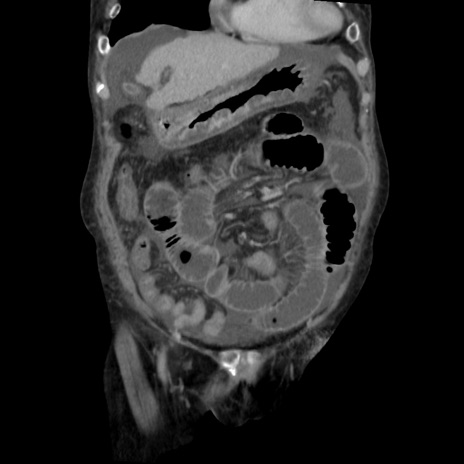

横断像